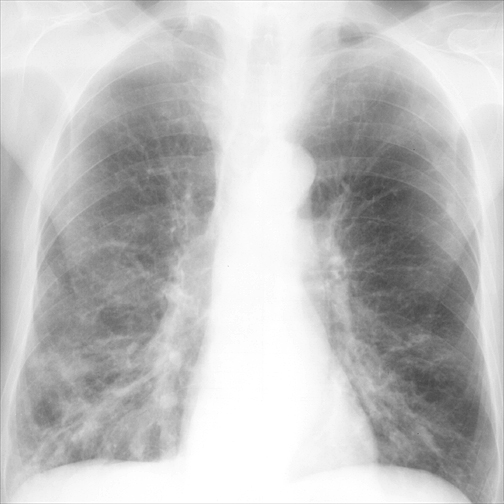

Bronchiectasis

Case 1 PA